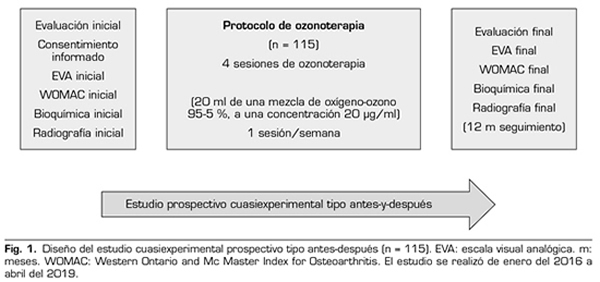

Se realizó un estudio cuasiexperimental prospectivo tipo antes y después. Se incluyeron en el estudio a 115 pacientes con artrosis de rodilla con Kellgren-Lawrence (KL) grado 2 o más, que asistieron al Hospital Universitario de Santa Cristina, con síntomas clínicos (dolor, rigidez, pérdida de la función), que requieren tratamiento conservador y en los que fracasó el tratamiento sintomático previo. El estudio se realizó de enero del 2016 a abril del 2019 y fue autorizado por el Comité de Ética del Hospital Universitario de Santa Cristina, previa firma de consentimiento informado (Figura 1).

En la evaluación inicial se explicaron los objetivos del tratamiento, el procedimiento, las indicaciones y las contraindicaciones, se realizaron la evaluación bioquímica inicial (análisis de PCR, VSG y ácido úrico), la radiografía inicial de rodillas, se proporcionaron las escalas de resultado clínico (EVA y WOMAC) y se firmó el consentimiento informado (Figura 1). No valoramos la movilidad articular en este estudio, porque no estaba considerada como variable de resultado.